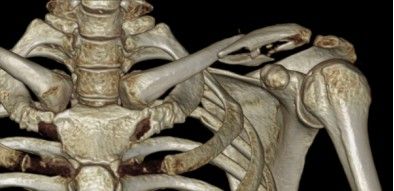

Клавица - это в форме. Проксимальная полугольная проекта проецирует спереди, оставляя место для нейросулярного пачка верхней конечности. Дистальная половина дуги проецирует назад (вогнутые), а затем соединяет лопатку (ростральный процесс и акромион). Переломы ключицы обычно возникают на соединении двух дуг (середина диаграмма), скорее всего, из-за отсутствия связок, прикрепленных к соседним костям в этом регионе, и потому что это самая слабая часть ключицы. Когда перелом ключицы смещается, проксимальный сегмент почти всегда тянет вверх (головокружение) из -за грудиноклеадомастоидной мышцы (прикрепленной к проксимальному конце ключицы), а дистальный сегмент вытесняется по нисходящему (ковш) по весу), и кнопленная первичная, первая, на »(IE), на одном), на одном), на одном), на одном), на одном), на одном), на одном), на » (IE), наглядно) Сокращение субскапуляриса и майора Pectoralis (которая внутренне вращает верх). В основном это связано с сокращением основных мышц Subscapularis и Pectoralis (которые внутренне вращают плечо и тянут его к груди).

Медиальные переломы ключицы часто бывают вне -тикулярными переломами с незначительным смещением и их можно лечить консервативно. Эпифиз медиального конца ключицы обычно закрывается в возрасте 23-25 лет и является последним эпифизом, который закрывается в организме. Следовательно, многие медиальные травмы на самом деле являются эпифизарными переломами тарелки со Сальтер-Харрисом типа I или II. Обычные рентгеновские снимки трудно диагностировать, с тем, что рентгенограмма наклона головки на 40 ° и сравнение со здоровой стороной может показать смещение медиального конца ключицы, а КТ обеспечивает наилучшую диагностическую визуализацию.